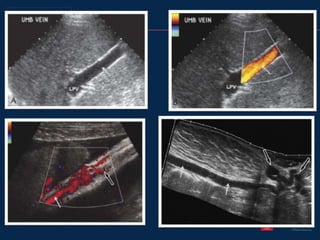

• #39 Enlarged recanalized umbilical vein. A, Sagittal view of the left lobe of the liver shows a dilated umbilical vein (arrow) measuring more than 10 mm in diameter. The left portal vein (LPV) is also seen. B, Similar color Doppler view confirming hepatofugal flow within the recanalized umbilical vein (arrow). Paraumbilical collaterals. Magnified sagittal color Doppler view of the inferior aspect of the left lobe of the liver Sonographic caput medusa. Sagittal panoramic view of the anterior abdomen shows a recanalized umbilical vein (white arrows) traveling inferiorly to the periumbilical region where it becomes quite tortuous (black arrows). This is the sonographic equivalent of a caput medusa.